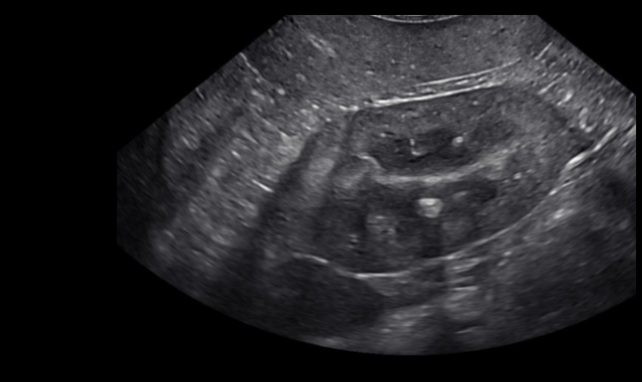

Liver

Kidney

Spleen

Urinary bladder

Small intestines